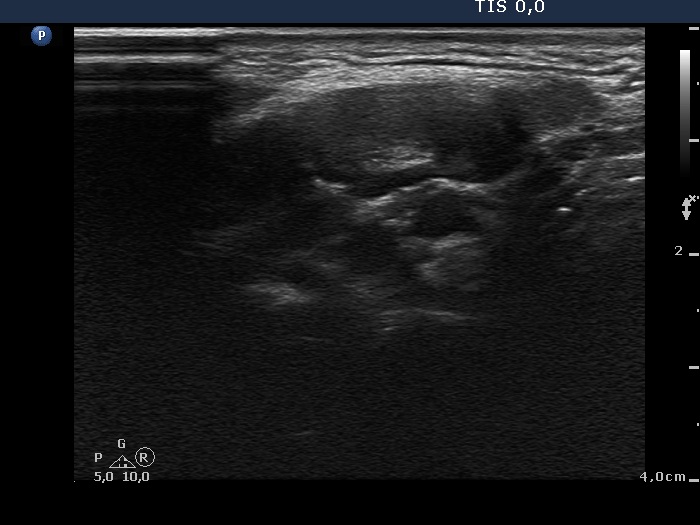

Ultrasonography: The thyroid was echonormal. There was a moderately hypoechogenic inhomogeneous nodule in the lower pole of the right lobe. There were two lymph nodes next to each other above the right thyroid in the submandibular area. The lymph nodes presented a regular hilum.

This is the typical presentation of a bacterially infected lymph node. In most of these cases we find multiple lymph nodes next or very close to each other. The presence of ill-defined hypoechogenic areas within the lymph nodes is an even more important sign of a bacterial lymphadenitis.

It is edifying to analyze the hyperechogenic figures in the thyroid lesion. While examining the patient, I interpreted these as microcalcifications. However, by preparing the case study I had to regroup these figures. These are in fact presentations of connective tissue and colloid crystals. (See the footnotes of the relevant images.)